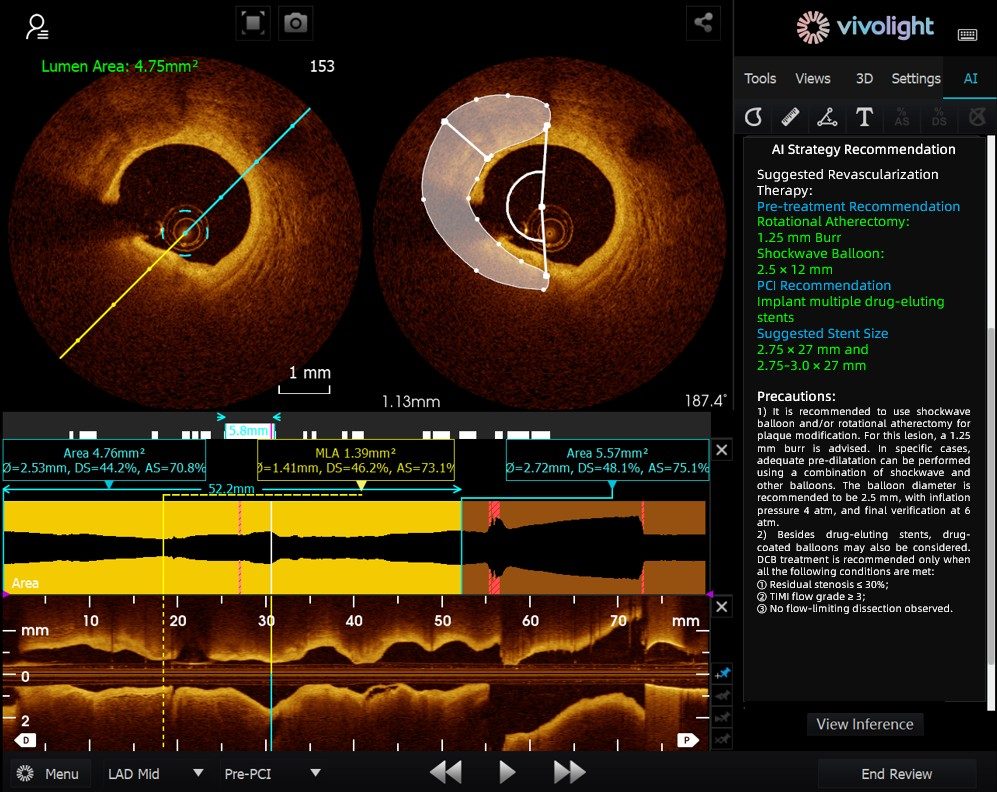

Sviluppato sulla base del sistema OCT di Vivolight Medical, AI-OCT è un sistema intelligente di supporto decisionale di nuova generazione per l'imaging intravascolare. Integra dati diagnostici di imaging intravascolare sparsi, tra cui diametro del lume, lesioni colpevoli, OCT-FFR e natura della placca, in strategie di trattamento complete e raccomandazioni attuabili. In quanto software di ricerca indipendente integrato nella piattaforma OCT, è sviluppato in collaborazione con diversi ospedali per creare versioni personalizzate su misura per specifiche esigenze cliniche.

Durante il forum all'avanguardia, gli esperti hanno sottolineato che il sistema AI-OCT rappresenta un passaggio radicale dalla "visualizzazione di immagini" alla "fornitura di piani di trattamento", affrontando le sfide del sovraccarico di informazioni e della complessità del processo decisionale nelle procedure interventistiche cardiache, che tradizionalmente si basano in larga misura sull'esperienza del medico. I principali vantaggi del sistema includono:

●Guida intraoperatoria in tempo reale: Organizza in modo dinamico le informazioni diagnostiche durante l'intervento chirurgico, fornendo parametri chiave e raccomandazioni cliniche.

●Processo decisionale basato sulle prove: Tutti i suggerimenti sono in linea con il consenso degli esperti e con le linee guida cliniche, garantendo rigore e affidabilità.

Il sistema AI-OCT adotta un'architettura "piccolo modello + big data + grande modello": i modelli piccoli consentono un'interpretazione precisa delle immagini, mentre i modelli grandi consentono un ragionamento clinico completo. Sfruttando database cardiovascolari di alta qualità e la tecnologia RAG (Retrieval-Augmented Generation), offre un supporto end-to-end, dalla valutazione della lesione allo sviluppo della strategia di trattamento.